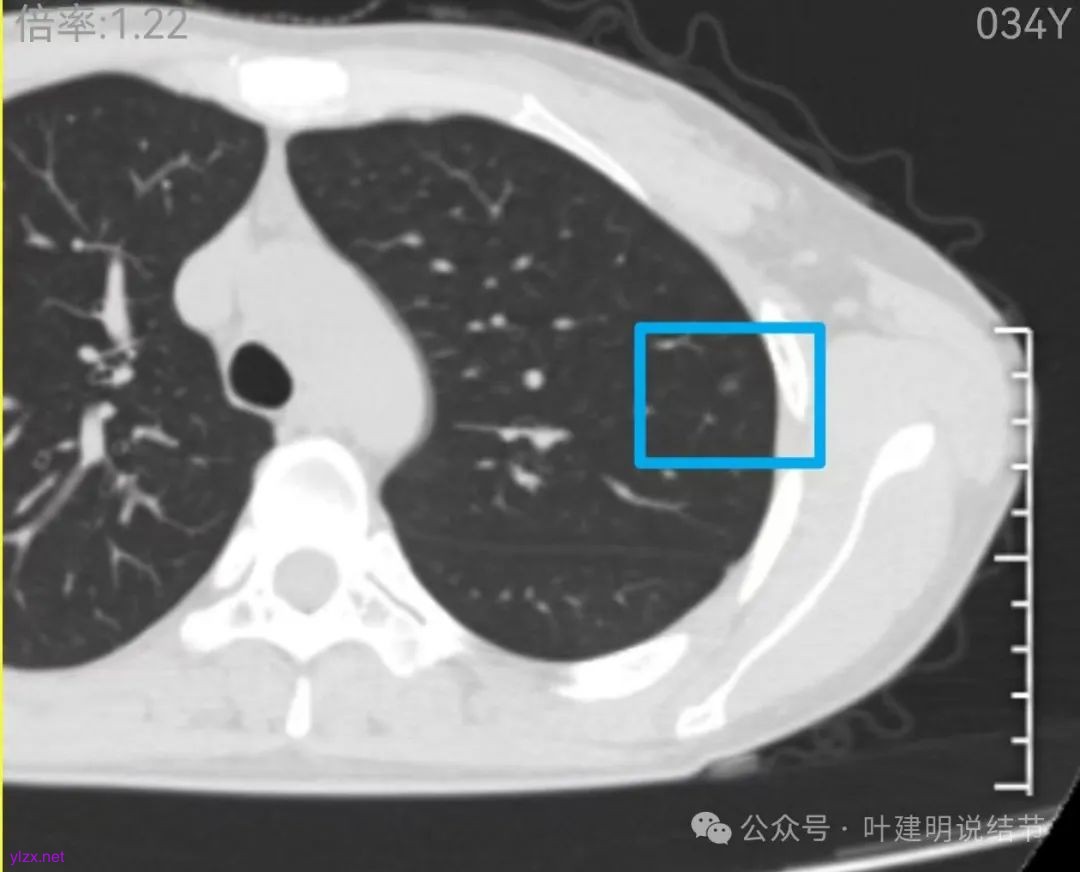

先来看2024年12月的影像:

左上叶淡而轮廓欠清楚的磨玻璃结节,缺乏聚拢性,没有收缩力。

在上叶淡而轮廓较清,密度不太纯略显杂乱的小磨玻璃结节。

两肺多发结节,左侧黄色标注的考虑是肺泡上皮增生可能性大;蓝色的考虑肺泡上皮增生或者少许慢性炎可能性大;右侧红色宽起来并带有红色箭头的这处是主病灶,偏混合密度,整体轮廓较为清楚,边缘显得毛糙,从2024年12月份的来看,要考虑是肿瘤范畴,原位癌或者微浸润性腺癌可能性较大,也不能完全排除不典型增生。但是在2022年的时候,这个病灶的边上也有一个实性的微小结节,如果只看2022年的,这么小的实性结节,又比较圆,表面也显得较为光滑,是要考虑良性的,当然太小了需要动态观察。回头再重新来看2024年底的,发现绿色箭头所指的这个微小实性的较2022年几乎没有变,去仔细寻找2022年的,发现当时在实性结节旁边也有密度很淡的一点磨玻璃影(也可能真的就是一处,只是扫描不够薄,密度的变化有些突兀而已),而到了2024年12月份,实性微小这处没有明显变化,但是原来很淡的磨玻璃变成了混合磨玻璃,范围也明显扩大。所以总体来看右肺下叶这处是考虑恶性的,而且从磨玻璃结节角度来讲,还是生长比较快的,就是说还是有一定风险的。加上左侧还有两处也是磨玻璃持续存在,虽然边缘轮廓显模糊一点,但多年以后也可能仍然要变成原位癌或者微浸润性腺癌之类的东西。通盘考虑以后,我倾向于右侧近期单孔胸腔镜下微创局部切除,左侧随访观察,等到有进展并风险增加再来考虑处理。意见供参考!